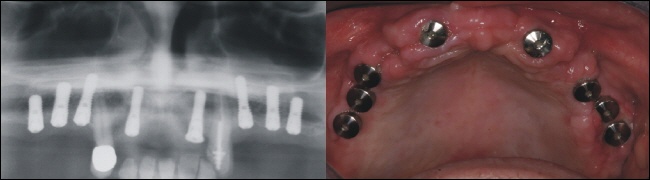

Implantation

Acht Implantate bieten im Oberkiefer eine solide Basis für eine festsitzende Brückenkonstruktion. Auf dem Bild oben rechts sieht man die Implantatkappen in der Mundhöhle. Die Implantate müssen nun wiederum 4-5 Monate im Knochen einheilen.